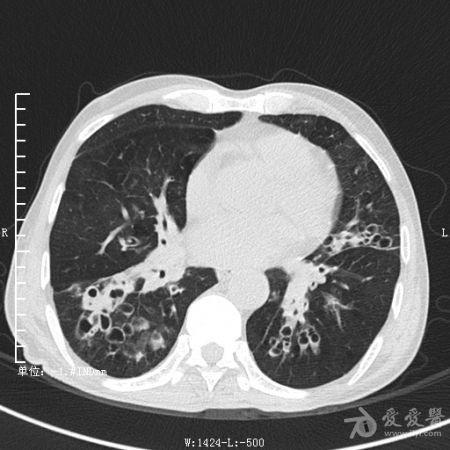

典型支气管扩张及肺水肿CT片

典型支气管扩张肺水肿